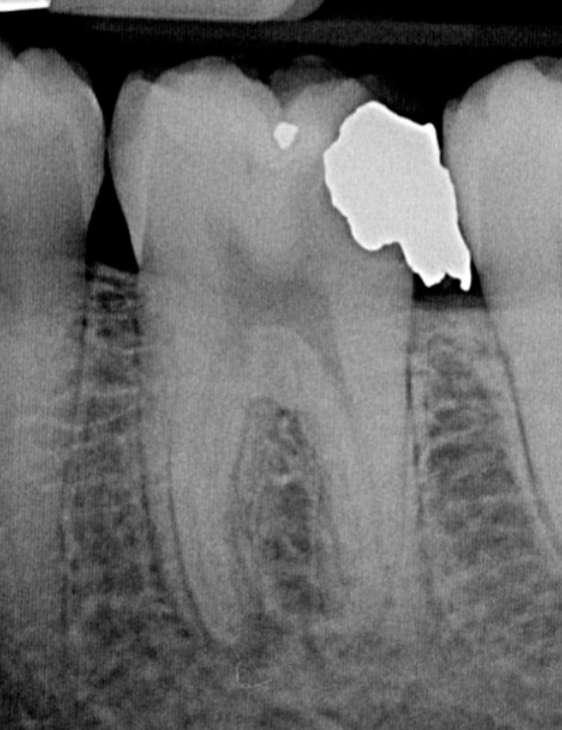

Zur koronalen Erweiterung der Kanäle wurde eine EdgeFile X7 der Größe 17.06 eingesetzt. Die Erstellung des Gleitpfads konnte rein mechanisch durchgeführt werden. Hierzu wurden EdgeFile X7 der Größe 17.04, 17.06 in alternierender Weise bis zum Erreichen der näherungsweise röntgenologisch bestimmten vorläufigen Arbeitslänge eingesetzt. Nach elektrometrischer Bestimmung der Arbeitslänge mit C-Pilot Feilen der Größe 8 und 10 erfolgte die weitere Präparation mit EdgeFile X7 der Größe 20.06, 25.06 und 30.06. Die Kanäle wurden nach der finalen Aufbereitung für 60 Sekunden mit 17% EDTA gespült. Die Abschlussspülung erfolgte schallaktiviert mit 6% NaOCl. Eine Masterpointaufnahme diente zur Verifizierung der Aufbereitung und der Passung der angepassten Guttaperchaspitzen (Abbildung 7). Nach Trocknung mit Mikroabsaugung und Papierspitzen wurden alle Kanäle in warm vertikaler Fülltechnik mit biokeramischem Sealer obturiert (Abbildung 8). Der adhäsive Verschluss erfolgte mit Bulk Fill Flow Komposit (Abbildung 9).

Abbildung 7: Masterpointaufnahme